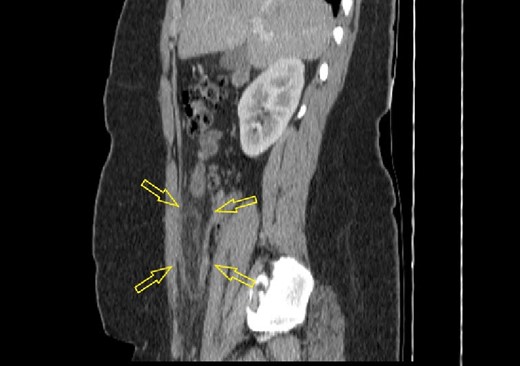

A 16-year-old female patient with obesity class III (body mass index of 41.5) presented to the emergency ward with abdominal pain for the last 48 h. No other comorbidities or previous abdominal surgery were reported. Physical examination was positive for lower right quadrant abdominal pain and for signs of local peritonism. The patient did not report loss of appetite, nausea, or vomiting. Laboratory analysis showed elevated serum levels of glycaemia of 6.48 mmol/l (normal range of 3.90–5.83 mmol/L) and C-reactive protein level of 63.30 mg/L (normal range of 0.00–5.00 mg/l). Abdominal ultrasonography failed to conclude the presence of intra-abdominal condition. Abdominal computerized tomography (CT) scan showed inflammation in the surrounding fat tissue of the pericecal region (Figs 1 and 2). No CT signs for acute appendicitis were present. Due to diagnostic uncertainty, an explorative laparoscopy was performed. Intraoperatively, a partial infarction of the right part of the great omentum was seen (Fig. 3). It was resected with a bipolar device (Video supplement S1) and appendectomy was performed additionally. Resected omentum and appendix were extracted via the umbilical port with minimal extension. The operative time was 65 min.

Sagittal abdominal CT scan (native series) showing intra-abdominal fat inflammation in the pericecal region (arrows).